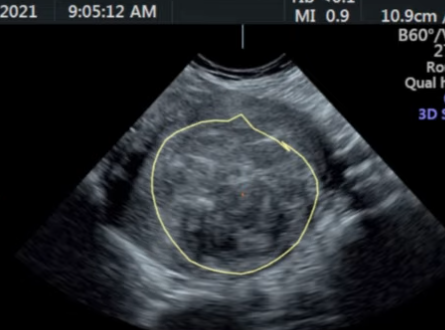

她的月经是正常的 这是一个叫Selva的医生在网上发表的第一例HIFU治疗子宫肌瘤的故事 《My first HIFU patient with fibroids》 临床结果的预测